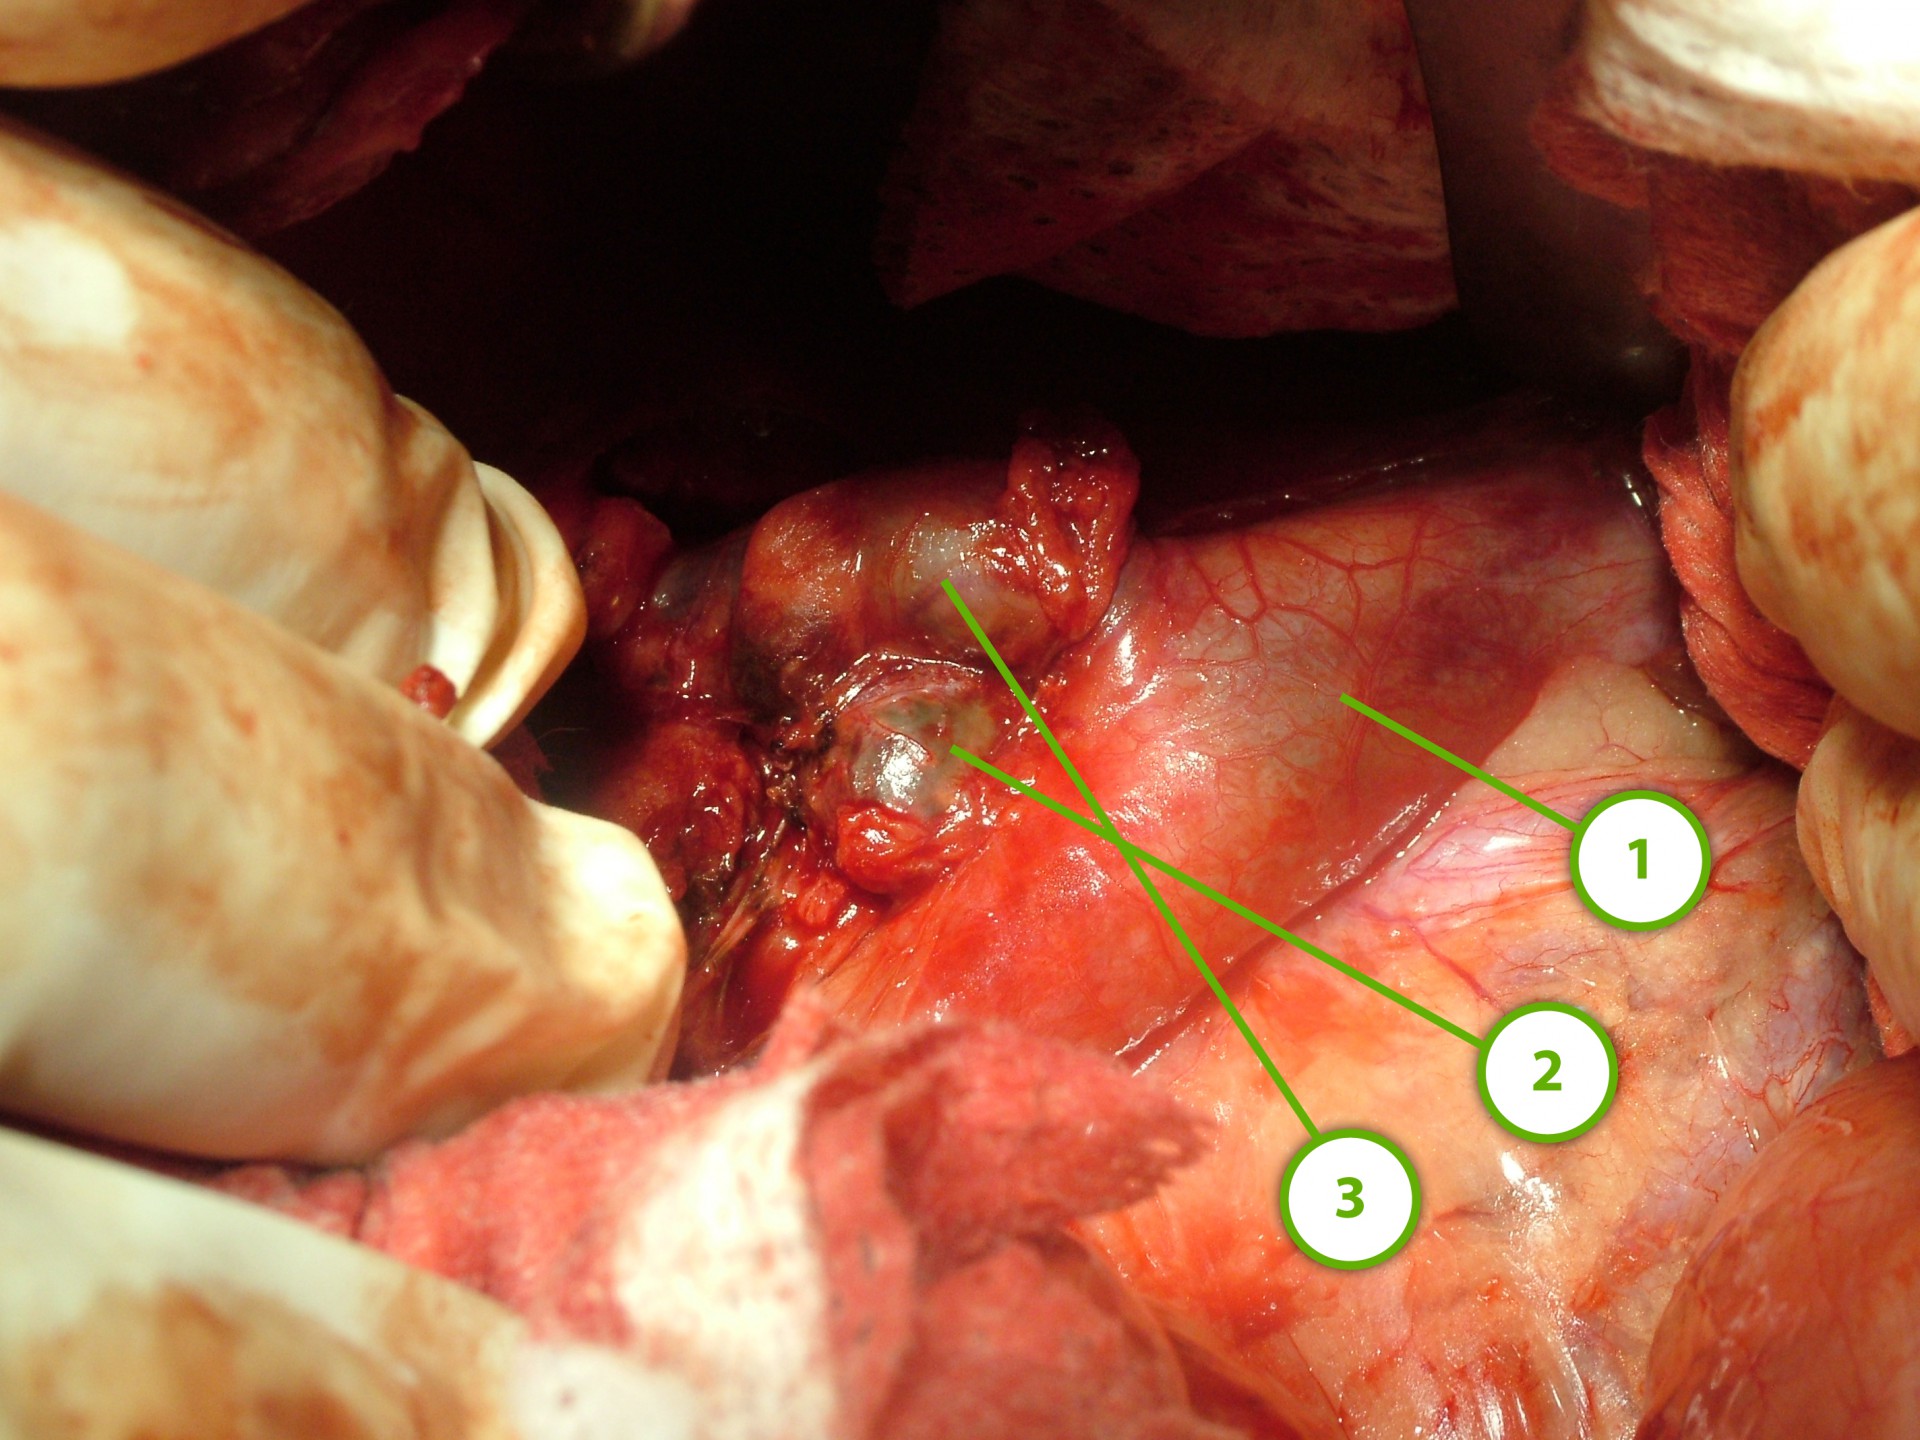

A műtét során az állatot az egészséges oldalára fektetjük és a hasüregbe bordaív mentén végzett metszéssel jutunk be.

A daganatos mellékvesét az azonos oldali vese előtti területen a bordaív alatt találjuk meg.

A mellékvese felett futó kisebb eret lekötjük és az elváltozott szervet a hasüregből eltávolítjuk. A jobb oldali mellékvese daganatos elváltozása esetén különös figyelmet kell fordítani arra, hogy az eltávolítandó szerv közvetlenül a hátulsó hasi vénán fekszik. Egyes esetben a daganat a hátulsó hasi vénába is besarjadzik, jelentősen csökkentve eltávolításának komplikációmentes lehetőségét.